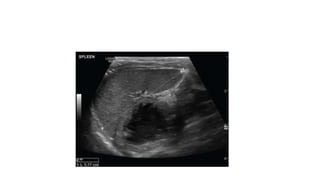

Normal Spleen Size In Adults

• The spleen can be measured using a maximum length from upper to

lower pole, which shoulder not exceed 13 cm.(Ref David Sutton)

• A thickness of 6 cm, measured from the hilum to the opposite edge, is

also a useful cut-off when the length is borderline.